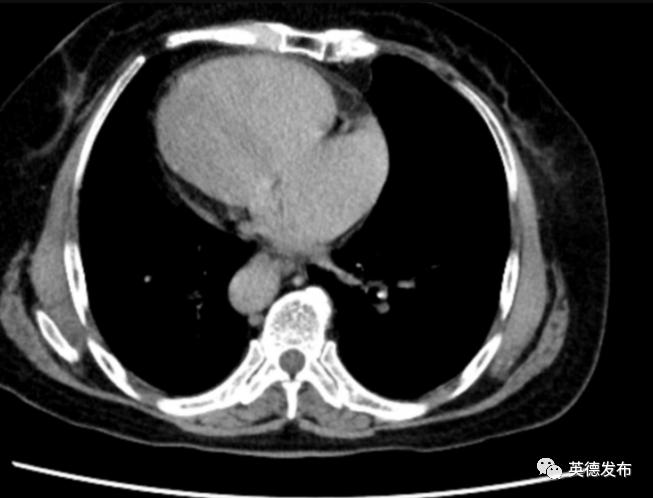

为进一步寻找“元凶”,医护团队充分做好相关应急预防措施,马上通过先进的80排160层螺旋CT,实施胸部血管螺旋CT血管成像(即“胸部血管CTA”),可见患者右肺上叶舌段动脉,左肺下叶动脉闭塞,余双肺各叶大部分闭塞,管腔明显狭窄,于是迅速作出诊断:大面积肺栓塞,已出现休克症状,患者随时可能死亡。